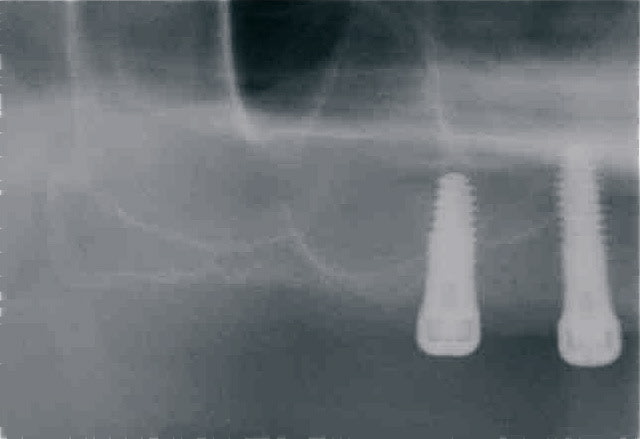

jumpingjackflash

premiers implants posées avec Pilot.

patient sous plavix impossible de suspendre le traitement

implant dans septum sinisien bridge posé en 2008

à main levé ; bonne chance